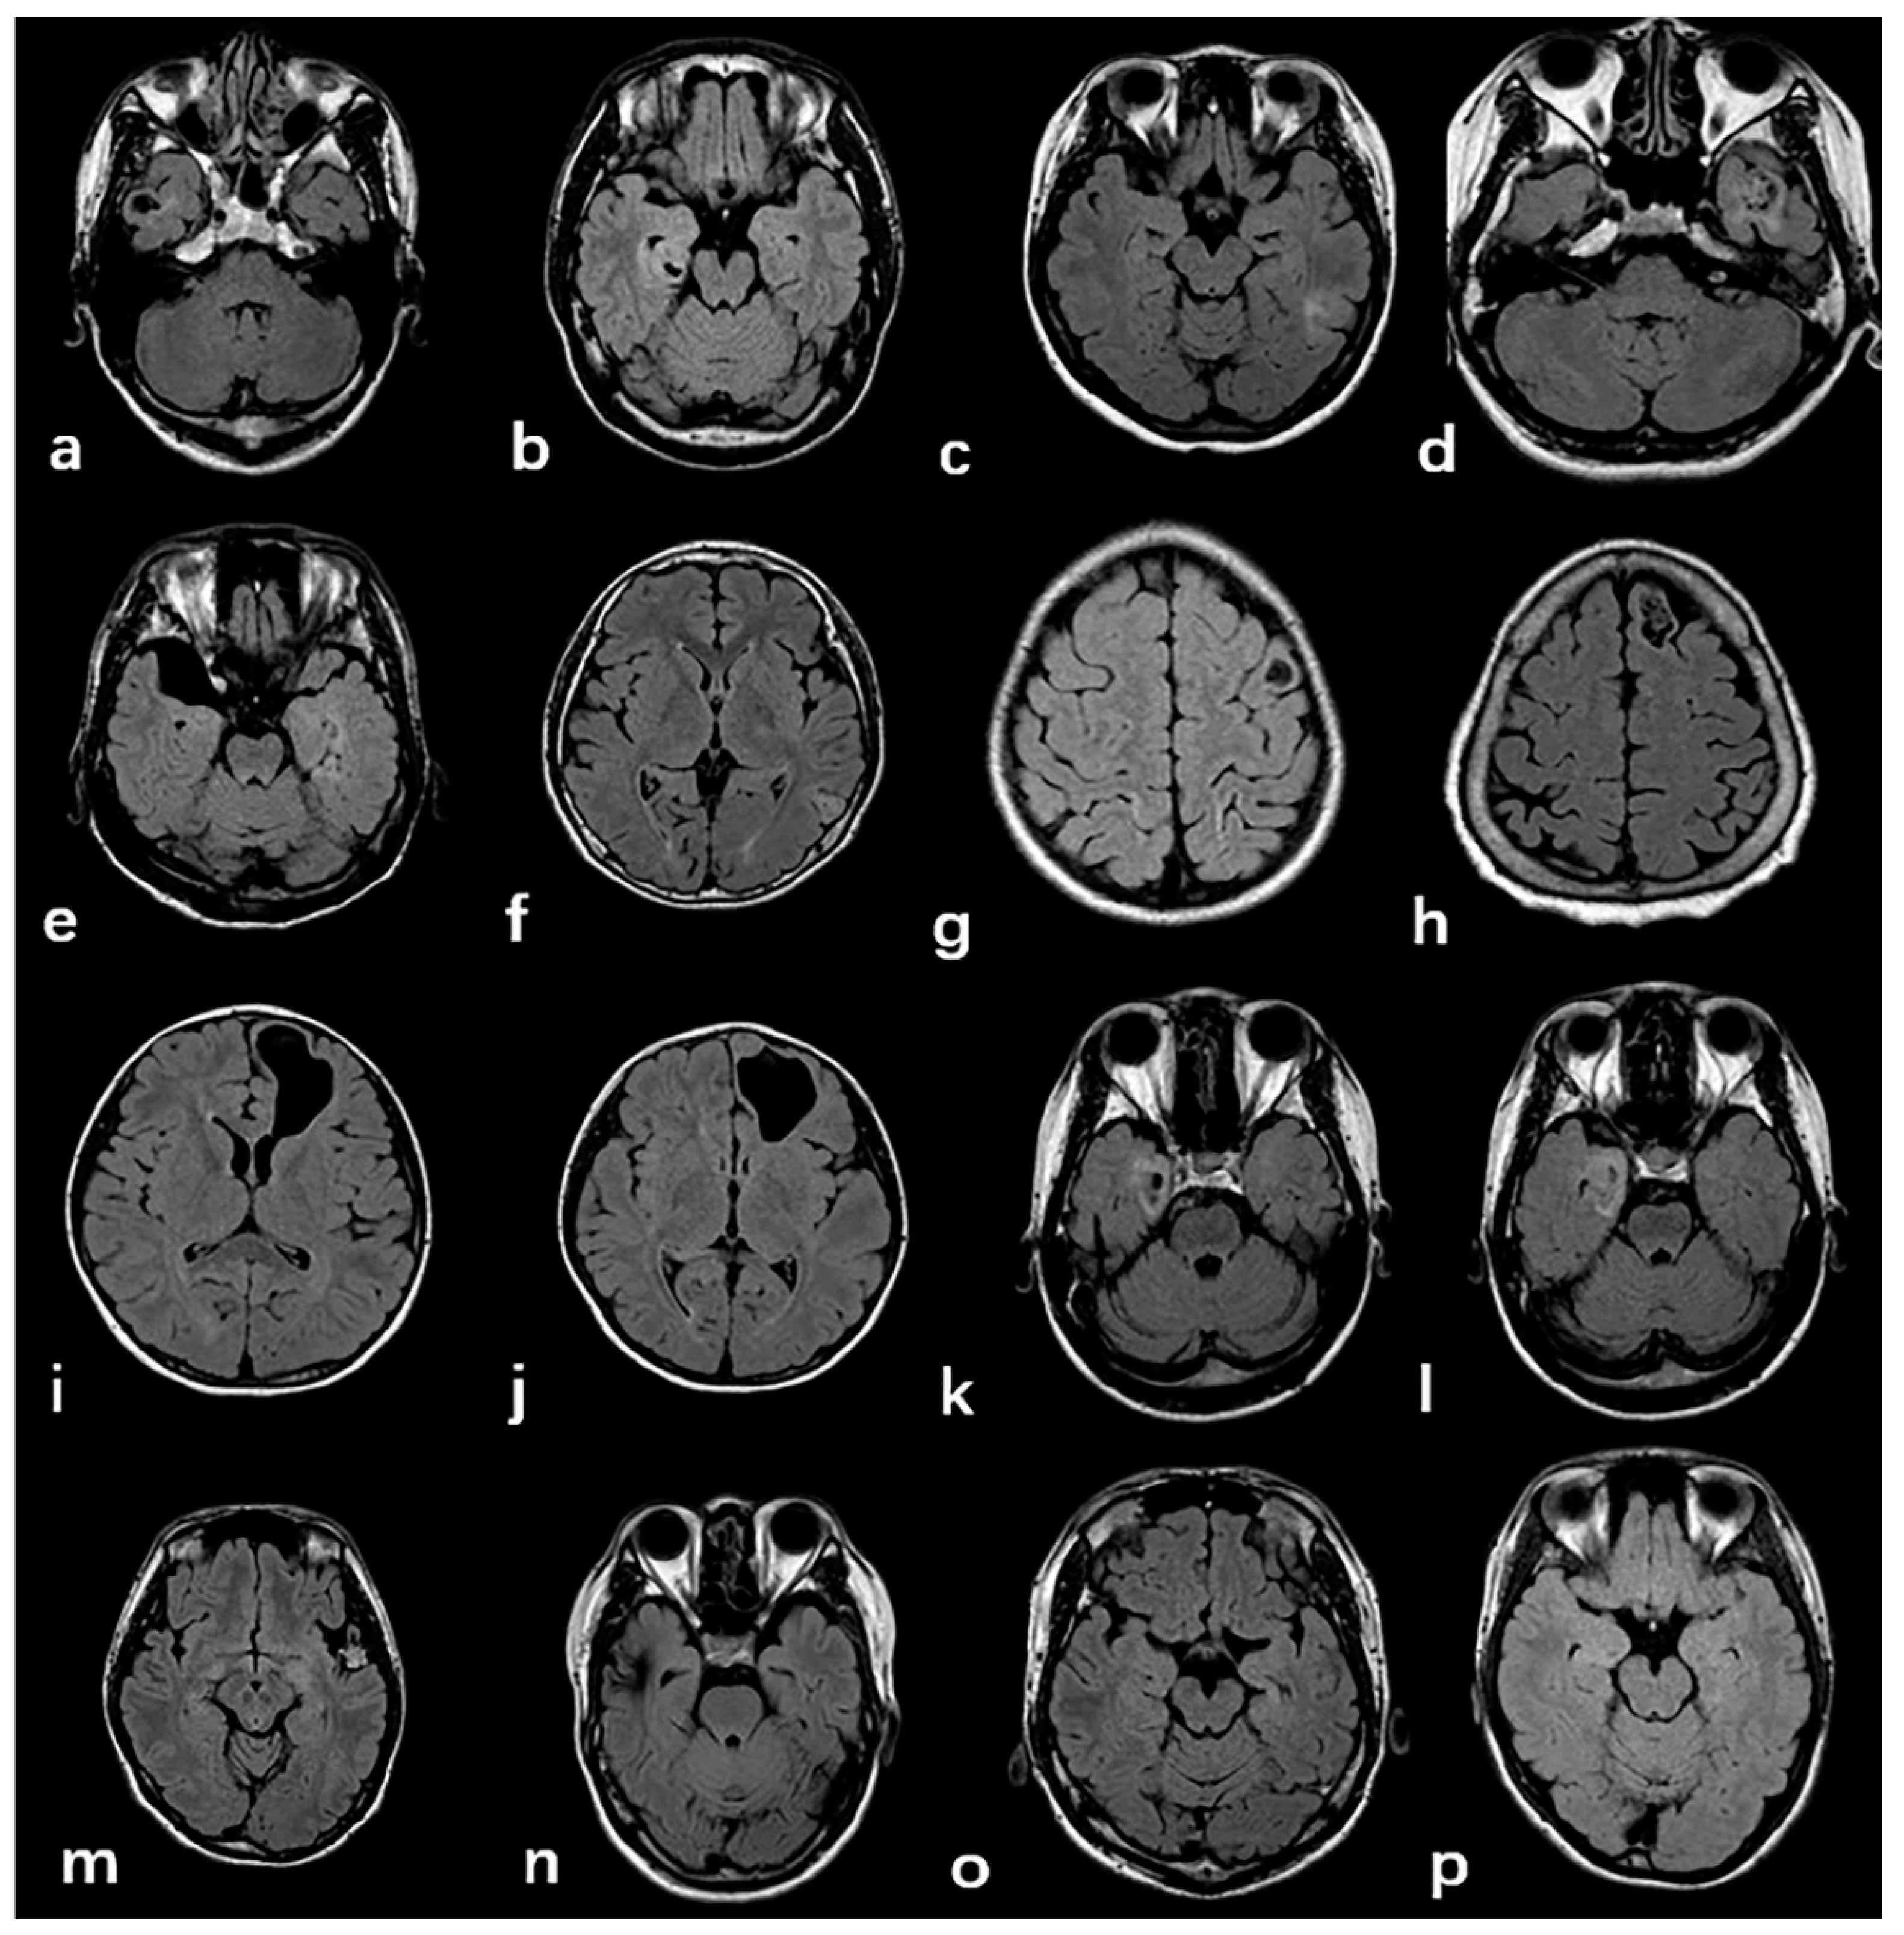

Typical imaging manifestations of FCD type Ⅲ are listed in Figure 3. The majority of tumors were located in the temporal lobe (n = 70, 84.3%) closing to the cortex, ten cases were located in the frontal lobe, two cases in the occipital lobe, and one case in the temporal occipital lobe. Four imaging patterns were differentiated in the low-grade, developmental, epilepsy-associated brain tumors, including a solid mass (n = 14, 22.9%), a predominantly cystic mass with an obvious mural nodule (n = 9, 14.8%), polycystic (n = 16, 26.2%), and mono-cystic (n = 22, 36%). Cerebral cavernous hemangioma malformations (n = 15, 68.2%) typically appear on T2W FLAIR sequences as a reticulated mixed-signal center with a surrounding hypointense rim, described as a popcorn pattern. A history of one case included an intracranial hemorrhage due to a cavernoma, which was surgically removed, but the magnetic resonance imaging of the brain revealed new cavernomas 1 year later, which were not identified in the previous imaging.

Figure 3.

Typical imaging manifestations of FCD type Ⅲ. (a–d):GG; Figure (e–h): DNET; (i–l): PGNT; (k–l): AG. The above low-grade developmental epilepsy related tumors were mostly found in the temporal lobe, adjacent to the cortex, and dominated by cystic components. (m): CCM, typical “popcorn” change. (n): AVM, particulate hypointensity in the proximal cortex; (o,p): HS, characterized by hippocampal atrophy and increased signal intensity.